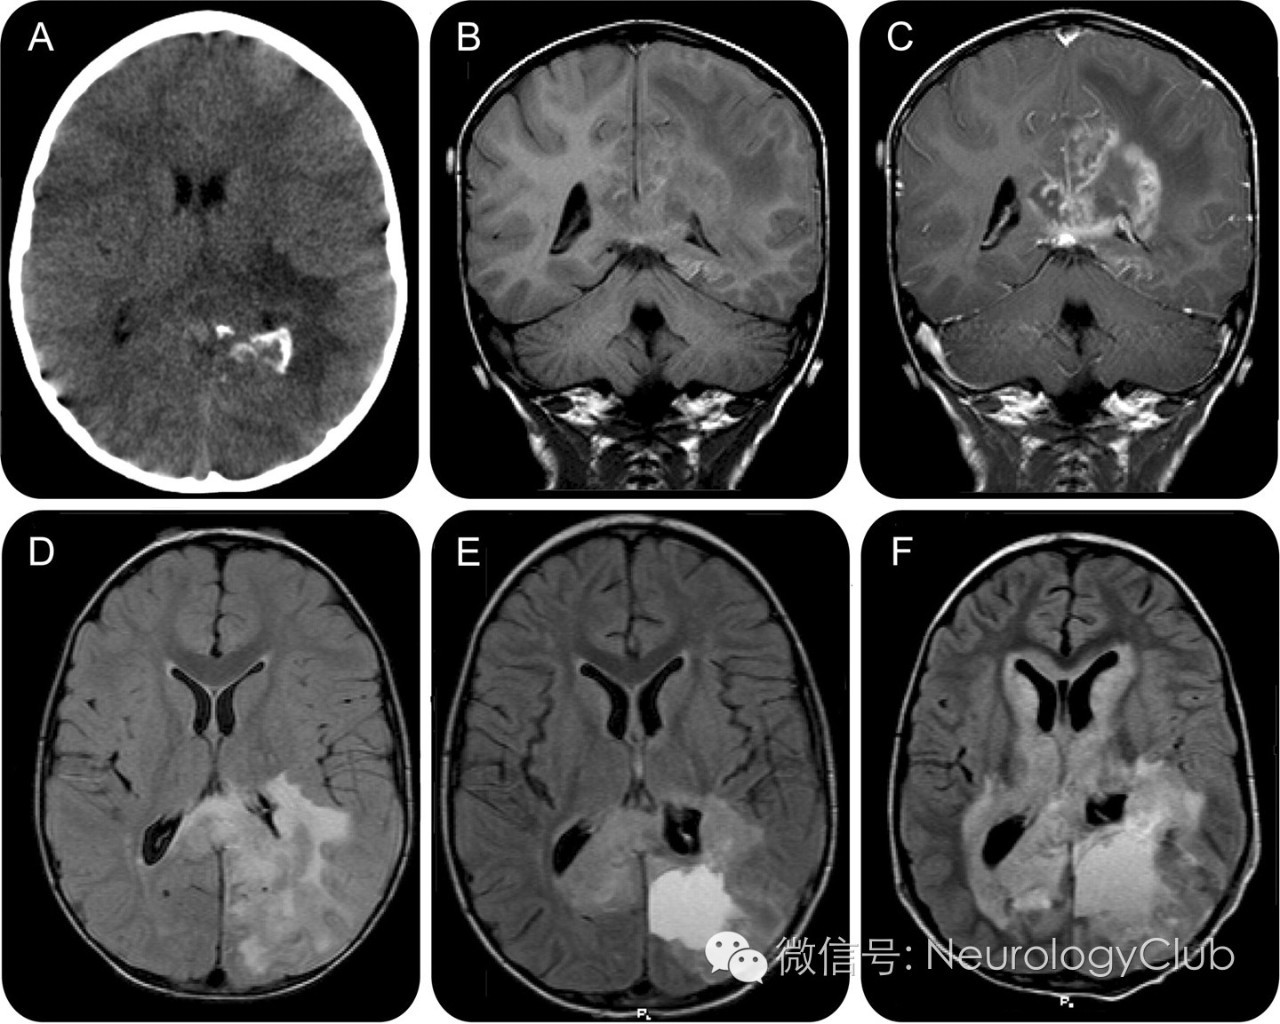

4岁男孩,表现为头痛2月。神经影像学提示部分钙化的左侧顶枕叶病灶,怀疑肿瘤(图1,A-C),活检提示为坏死性肉芽肿性脑膜脑炎。术后MRI提示病灶迅速进展(图1,D-F)。患儿出现发热和癫痫发作,3周内死亡,尽管用了万古霉素,头孢他啶,甲硝唑,两性霉素和氟康唑等药物。尸检提示为狒狒巴拉姆希阿米巴(Balamuthia mandrillaris,图2)。

(图1:A:CT上可见部分钙化的肿块;B-C:T1WI和T1增强可见周围不规则强化病灶;D-F:FLAIR可见病灶逐渐进展[活检前后])